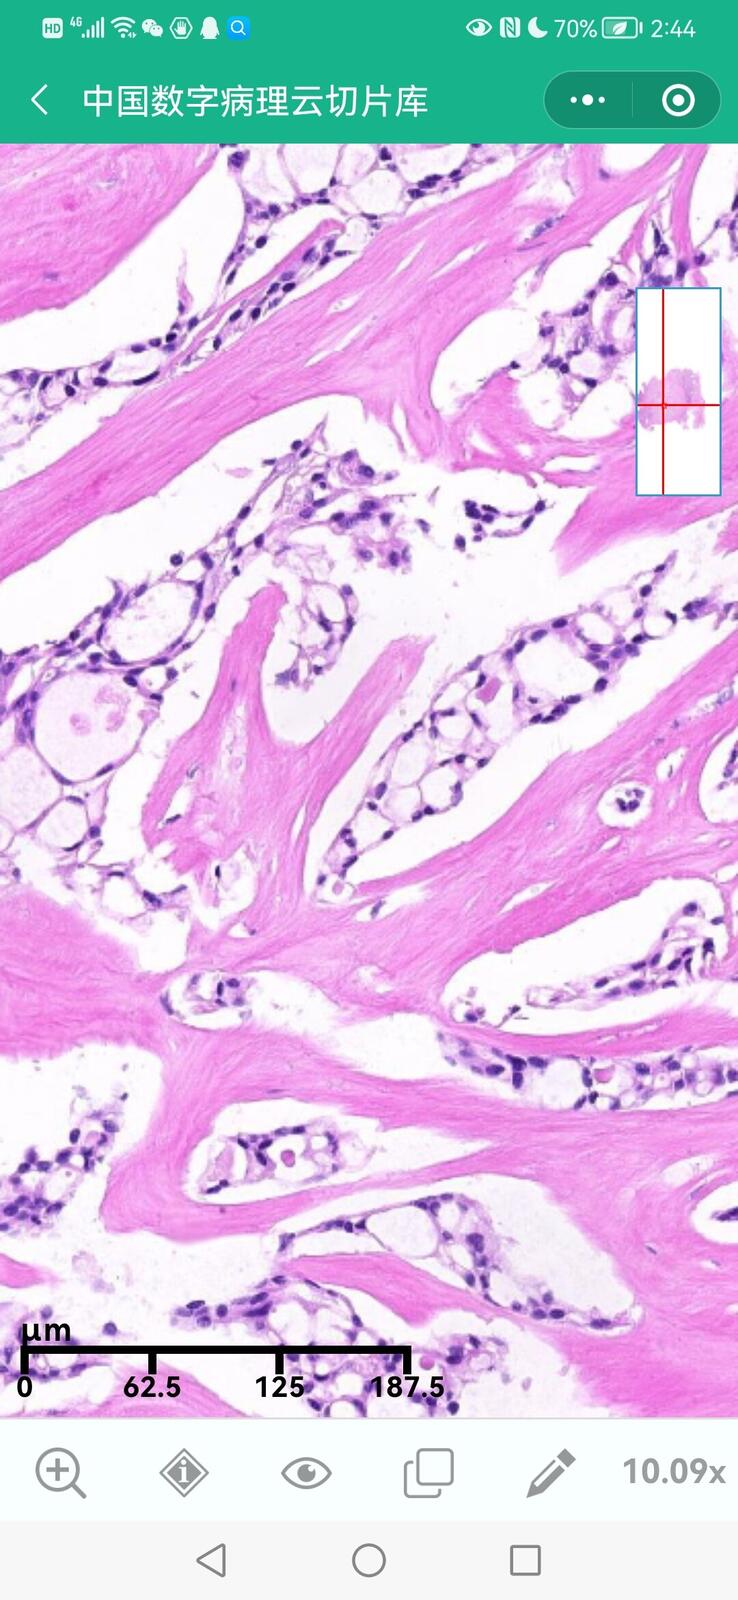

乳腺黏液性囊腺瘤伴导管内癌

乳腺多形性脂肪肉瘤

乳腺叶状囊肉瘤

乳腺分泌性癌(29岁)